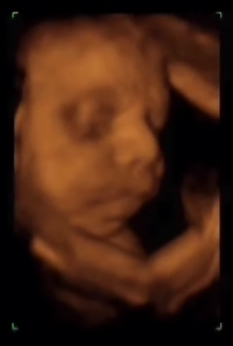

29 semanas y 2 días

Observen como y va teniendo cara mas de bebé. Observen como abre la boca. Normalmente suelen tener los ojos cerrados pero hemos observado en alguna exploración como los abre.